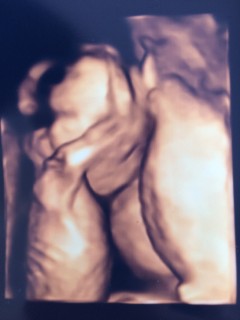

初3D、 babyはすごく元気でした。 性別は分かりませんでした(。-_-。)

手をバタバタ動かして、とっても可愛かった。でも、恥ずかしがりやさんで、お顔はなかなか見せてくれませんでした。 先生には、多分女の子だねと言われました!